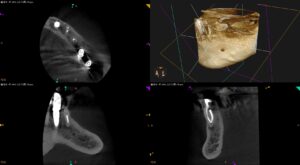

紹介患者さんの治療。 主訴は、 左下奥歯昨年の11月から治療を継続しているが終了しない。痛みが取れない… である。 歯内療法学的検査(2025.4.17) #21 Cold N/A, Perc.(+), Palp.(-) … 続きを読む 左下奥歯昨年の11月から治療を継続しているが終了しない。痛みが取れない…〜#21 Re-RCT 1回法